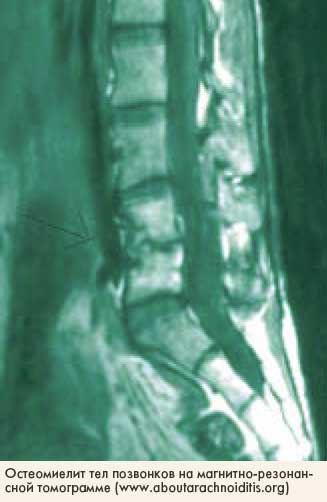

МРТ для диагностики инфекционно-воспалительных процессов МРТ для диагностики инфекционно-воспалительных процессов

На Европейском конгрессе радиологов, который прошел в марте 2004 года в Вене (Австрия), был представлен доклад, посвященный сравнительному анализу диагностических методов инфекционно-воспалительных процессов мягких тканей, костей и суставов на ранних стадиях развития. Акцент был сделан на преимуществах современных возможностей магнитно-резонансного исследования.

С помощью компьютерной томографии можно обнаружить скопление газа, выявить зону отека в мягких тканях уже на ранних стадиях процесса, но метод менее информативен, чем магнитно-резонансное исследование, позволяющее, кроме того, определить степень и тип изменений в тканях с помощью современных возможностей обработки изображений и анализа характера регистрируемых сигналов. В настоящее время ЯМР также успешно используется для ранней диагностики инфекционно-воспалительных процессов, локализующихся в костной ткани и суставах.